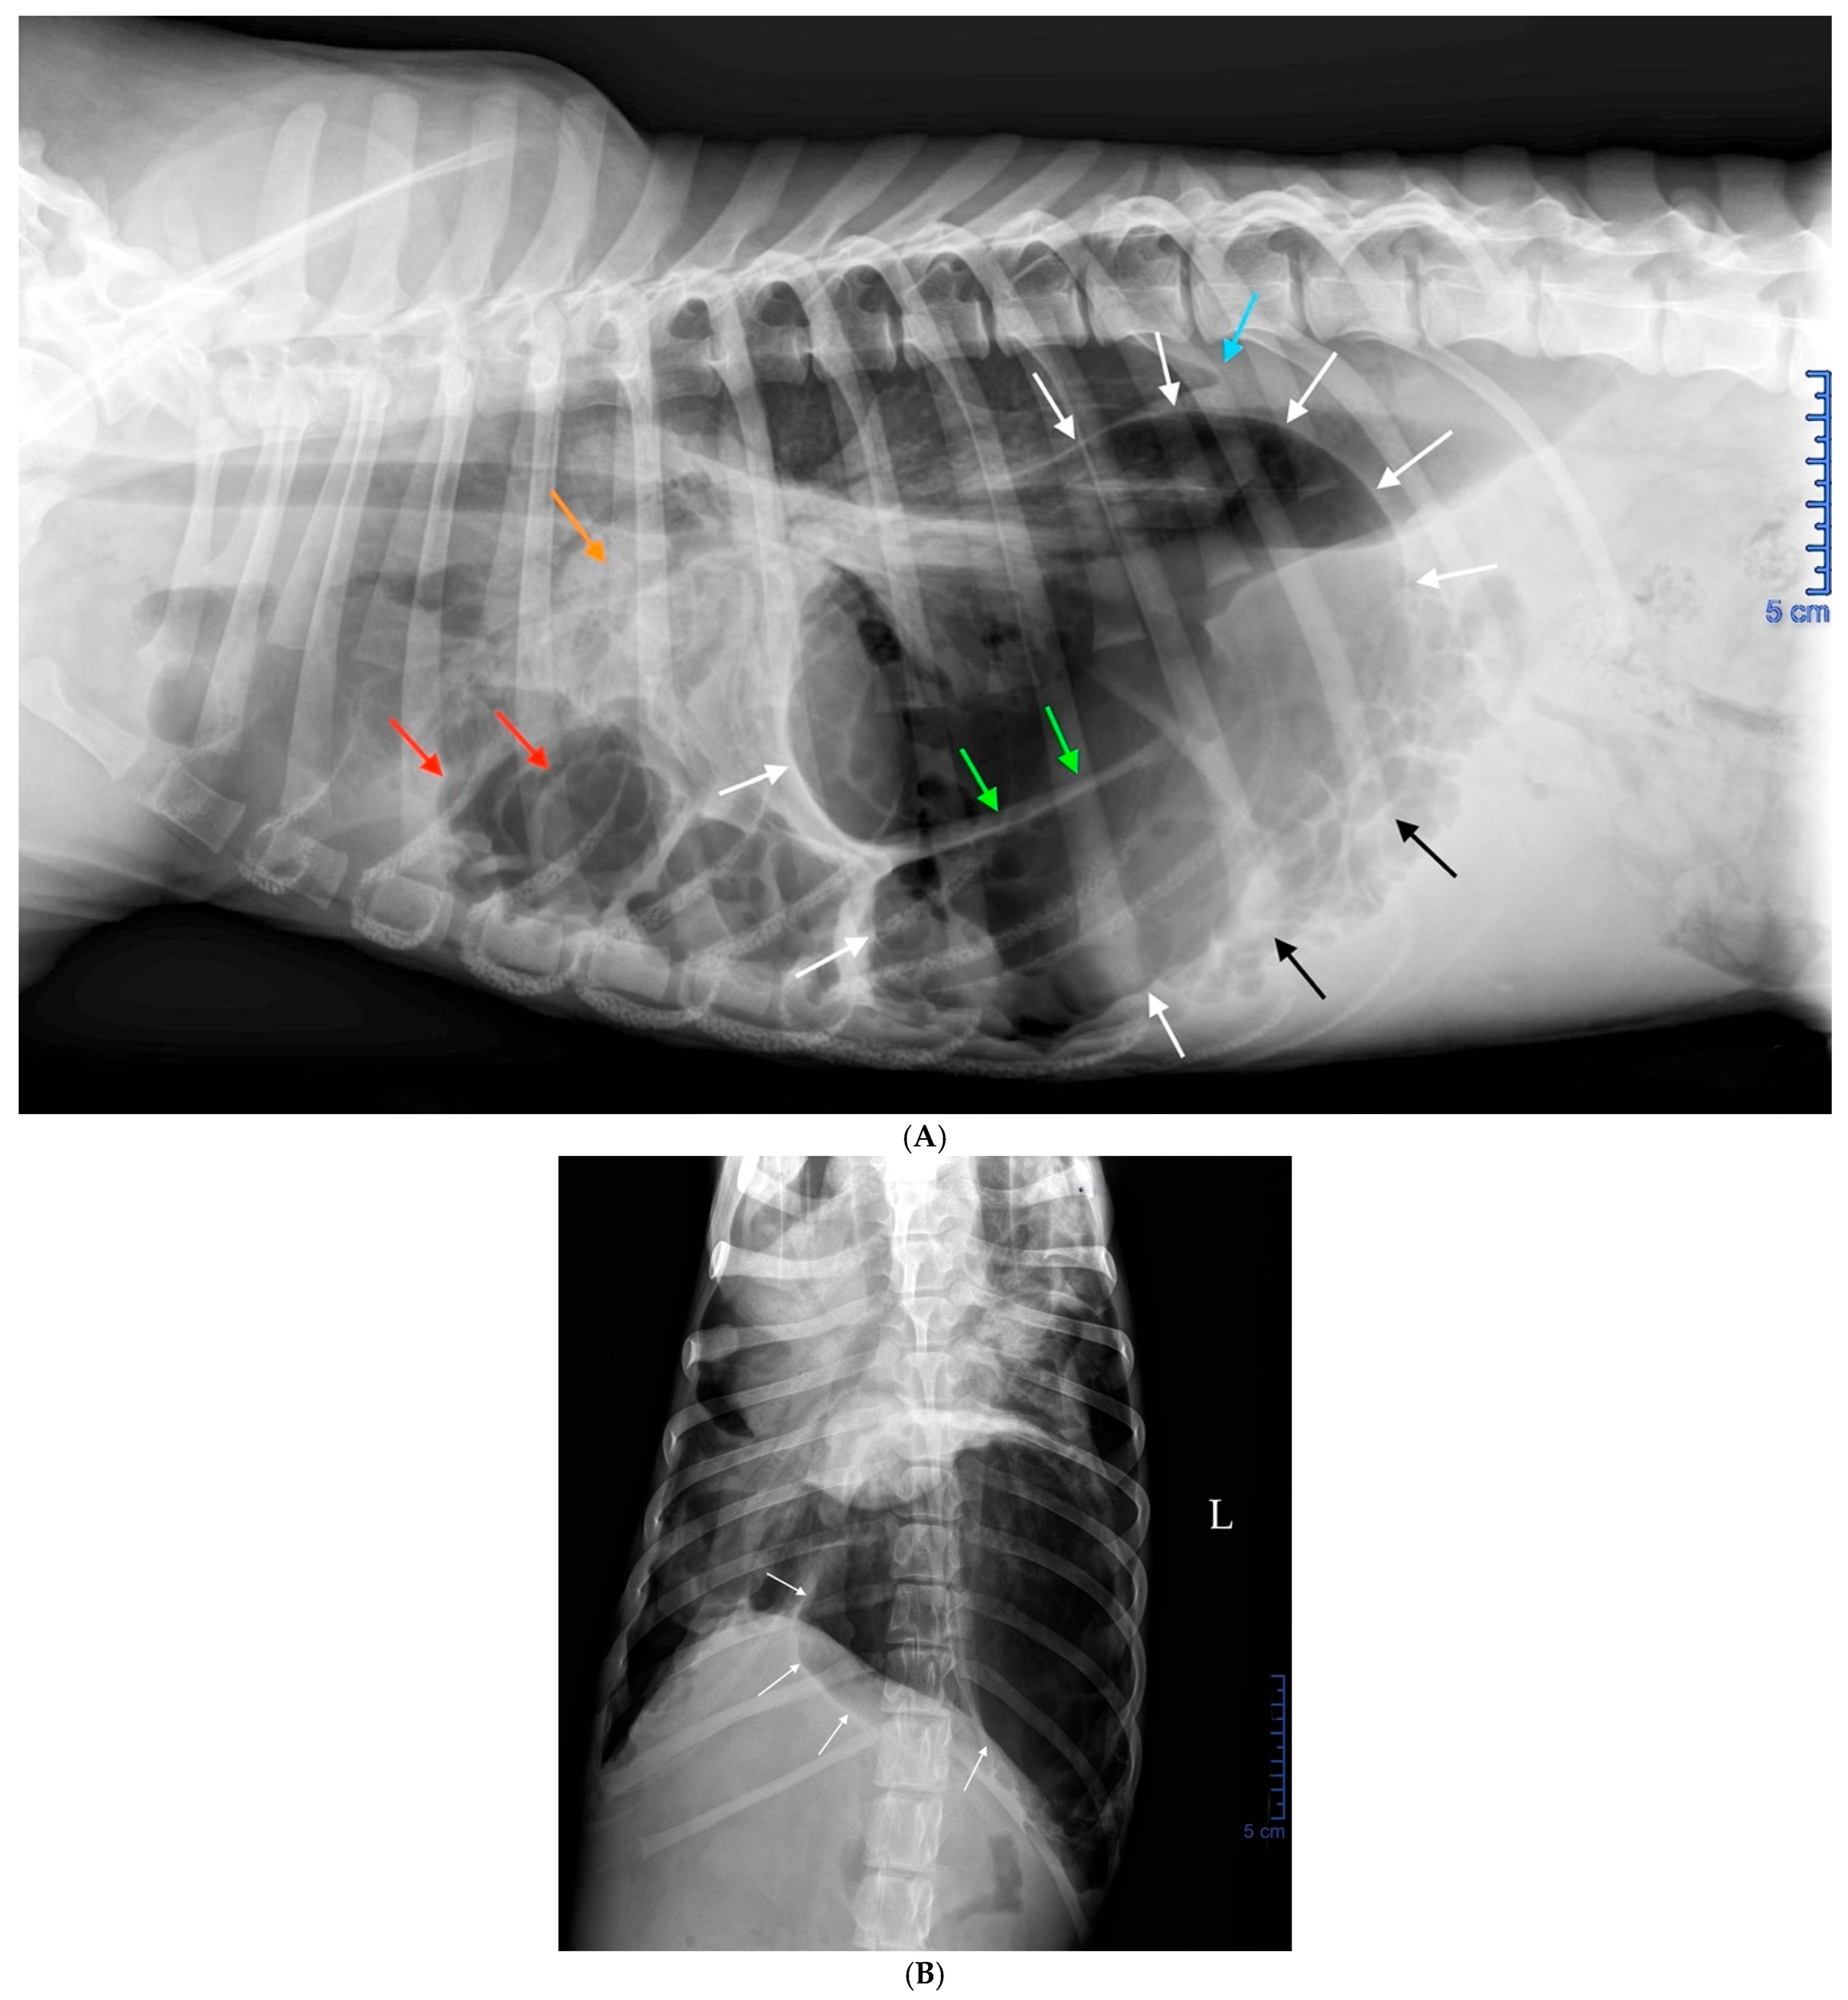

2.3. Radiographic Findings

2.4. Diagnosis